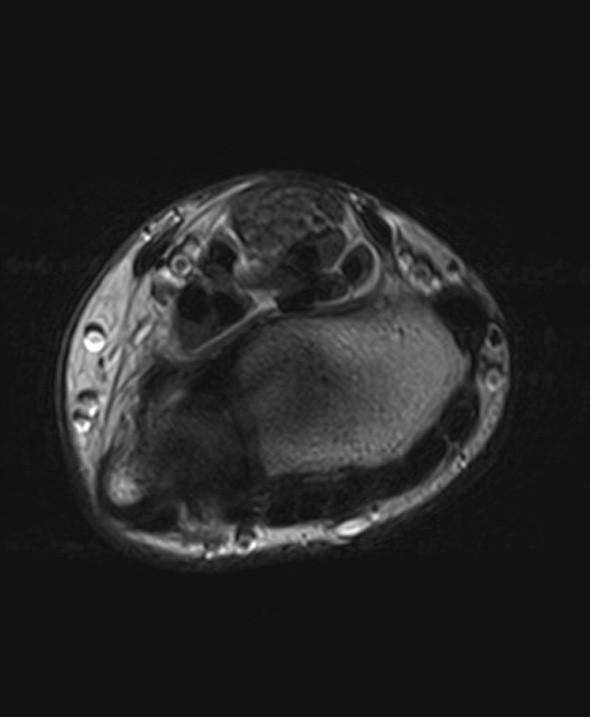

A previously healthy teenage girl was referred to the department of hand surgery with a lump on the flexor side of the left wrist. The lump had been discovered by the girl’s mother around seven years earlier and had gradually become increasingly painful. The patient described hypersensitivity to touch and numbness in the thumb, index, middle and ring fingers. Percussion over the tumour produced radiating pain and increased numbness in the same fingers. MRI showed an enlarged median nerve with a cable-like appearance due to fibrous thickening of the peri- and endoneurium and increased fat separating the roughly 15 nerve fibres (images online). The tumour was approximately 10 cm in size. A lipofibromatous hamartoma was diagnosed on the basis of the MRI findings, which are pathognomonic for the condition (1).

Surgical exploration of the tumour was performed, along with carpal tunnel decompression. At its widest point the tumour (see image) had a diameter three times the size of a normal nerve. At check-ups two and six months later, the patient was still experiencing the same pain as prior to surgery, but sensation in the fingers had improved. Neurography after two months showed moderate axonal and demyelinating sensorimotor neuropathy of the median nerve at the level of the wrist and carpus, suggesting compression neuropathy. EMG examination revealed sparse denervation activity and findings consistent with reinnervation. There were no previous examinations with which to compare the results.